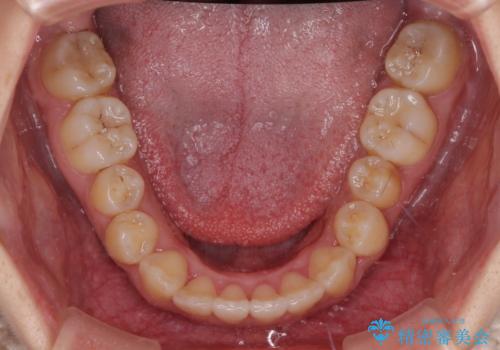

急速拡大装置による上顎骨の側方拡大が思った以上にうまくいき、非抜歯での矯正が可能となりました。

内側に倒れていた下顎の臼歯は起き上がり、清掃性も大幅に改善されました。